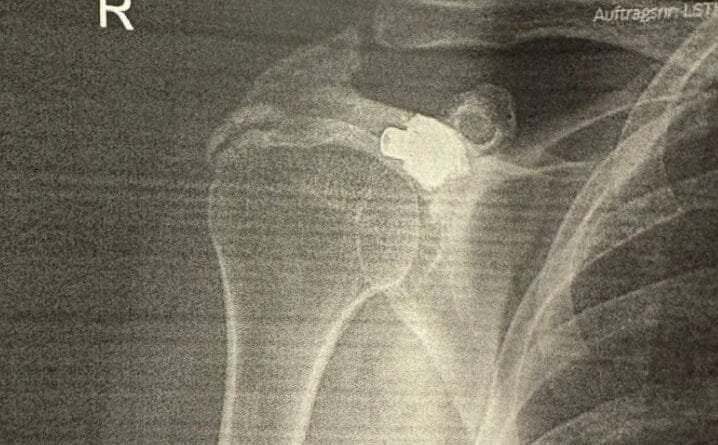

Pas analizave dhe fotografimeve, mjekët konstatuan diçka të jashtëzakonshme. Në krahun e djathtë të tij ndodhej plumbi i marrë 27 vjet më parë.

Sipas tyre, plumbi kishte depërtuar nga krahu i majtë në të djathtin, pa prekur asnjë organ vital, duke qëndruar i fshehur në trupin e tij për më shumë se dy dekada.